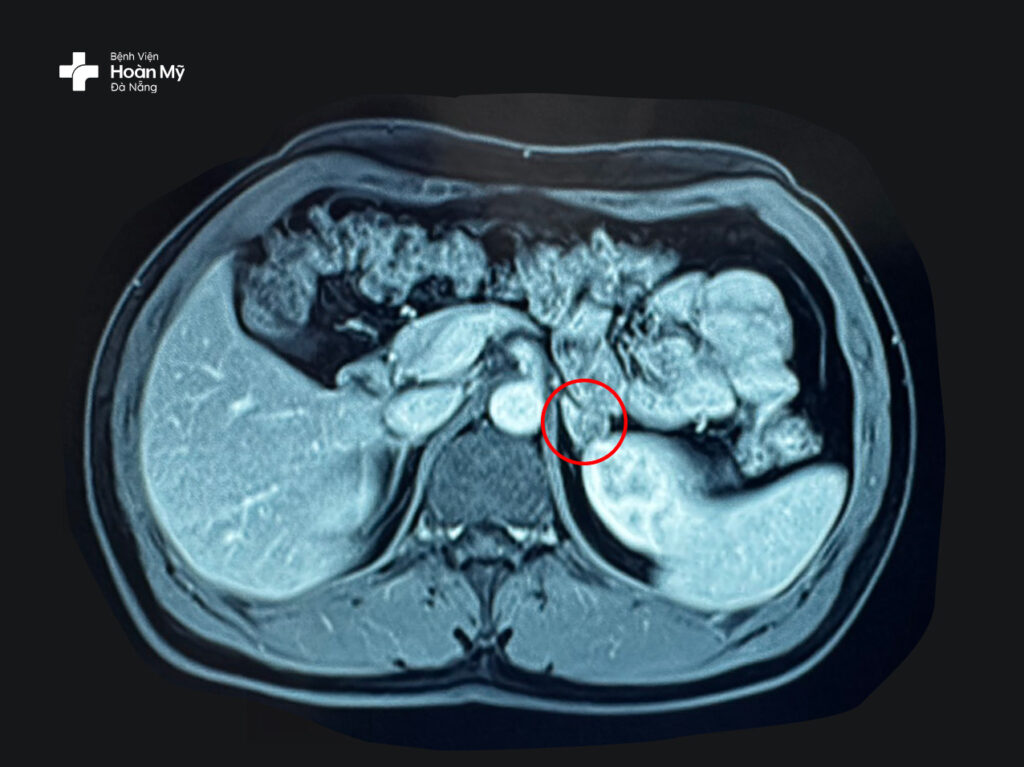

Các bác sĩ khoa Ngoại Tiết niệu – Nam khoa nhận định khả năng cao mỏi yếu cơ, hạ kali máu là biến chứng của bệnh lý này. Kết quả chụp MRI cho thấy có khối u trái, kích thước 12x16mm

Hình ảnh khối u tuyến thượng thận nhỏ được thể hiện rõ trên MRI